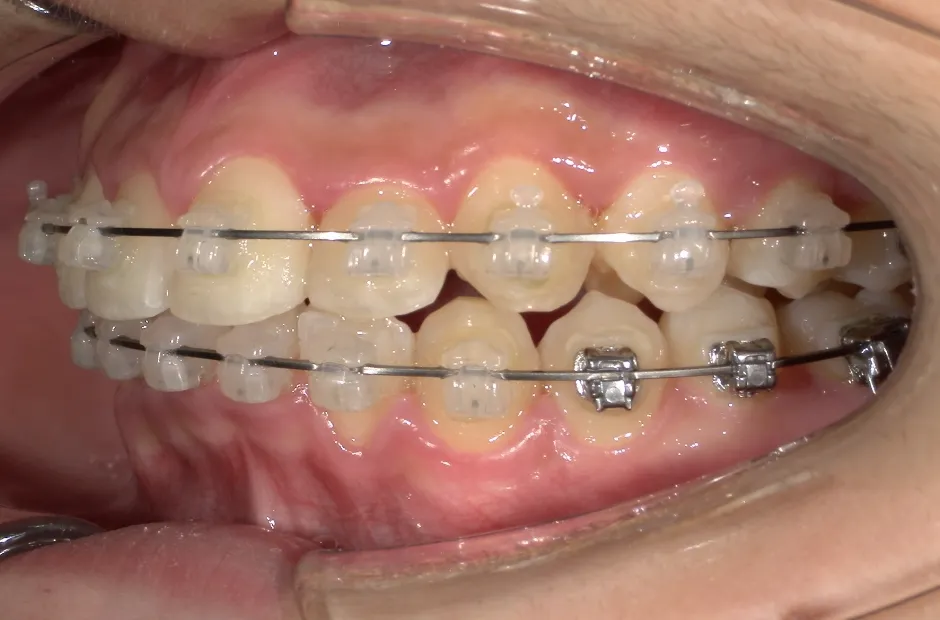

治療症例

ブラケット矯正

前歯部反対咬合

| 診断名・主訴 | 前歯部反対咬合 |

|---|---|

| 年齢・性別 | 14歳・男性 |

| 治療期間・回数 | 1年2か月 |

| 治療に用いた主な装置 | ブラケット矯正 |

| 抜歯部位 | なし |

| 治療費 | 60万円(税抜) |

| リスク・副作用 | 装置による違和感・疼痛・歯肉退縮・歯根吸収・虫歯のリスクなど |

治療中